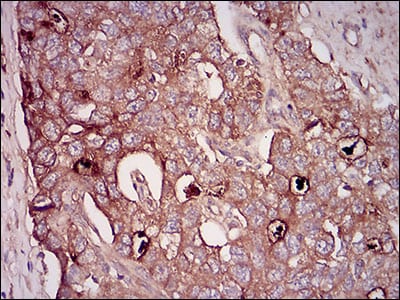

分类: 科研抗体货号: 30622别名: GDF8; MSLHP应用: IHC反应种属: Human